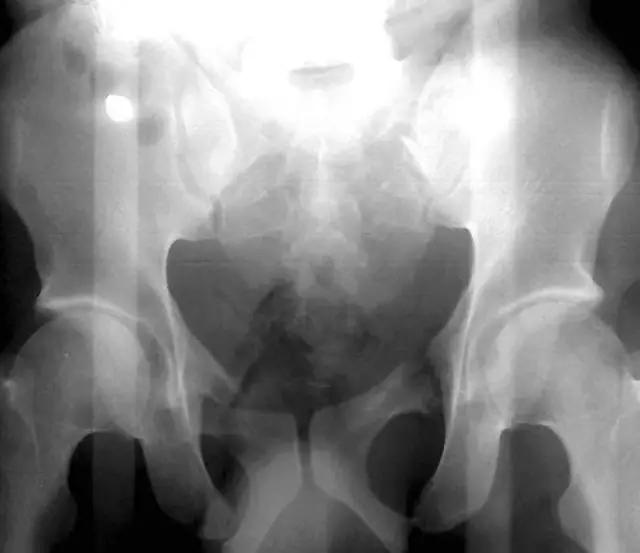

2. Malgaigne 骨折 (bucket handle 骨折,即桶柄骨折)

不稳定性骨盆骨折伴有前方和后方的骨折线累及髋关节。

(来源:radiopaedia)